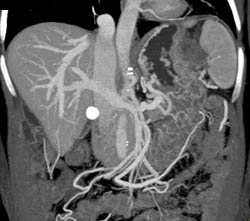

GIST Tumor With Ulceration